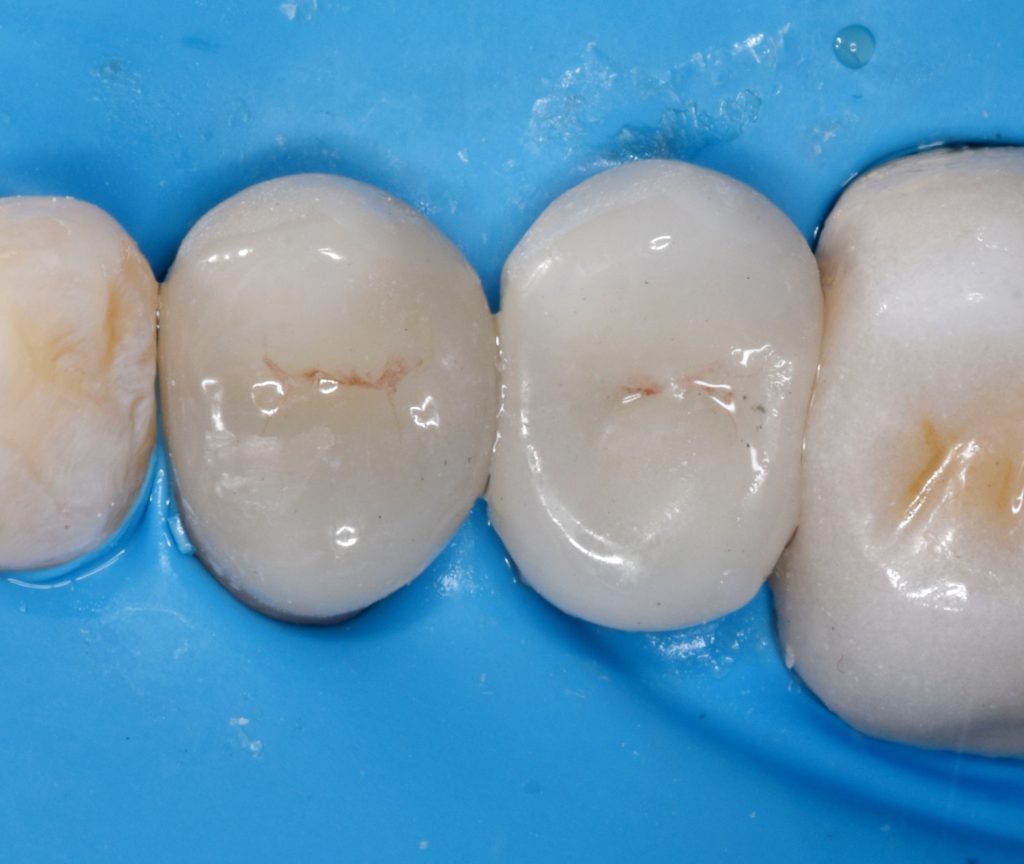

Upper right first and second premolars

Were badly decayed

Upon examination

I decided to go for indirect lithium disilicate restorations

Rubber dam isolation is mandatory in such cases

And final design to receive to monolithic lithium disilicate restorations